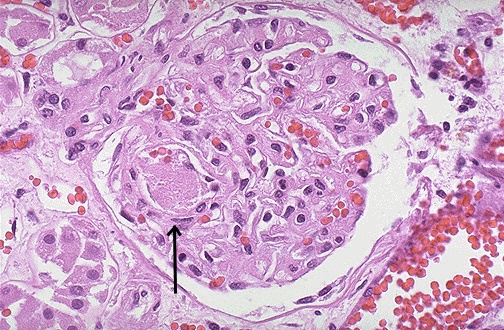

| A small platelet-fibrin thrombus is seen in a glomerular capillary above the arrow. This occurred in a patient with thrombotic thrombocytopenic purpura (TTP). This rare coagulopathy mainly affects kidneys, heart, and brain with small arteriolar thrombi. Acute renal failure can occur. The classic pentad of fever, acute renal failure, neurologic changes, thrombocytopenia, and microangiopathic hemolytic anemia is often present. TTP results from a congenital or more often acquired defect in the ADAMTS-13 metalloproteinase enzyme that cleaves vonWillebrand factor (vWF) multimers, and the large multimers lead to abnormal platelet aggregation. TTP overlaps with hemolytic uremic syndrome (HUS) that may be precipitated by verotoxins from such organisms as E. coli (type O157:H7) that cause endothelial injury. |